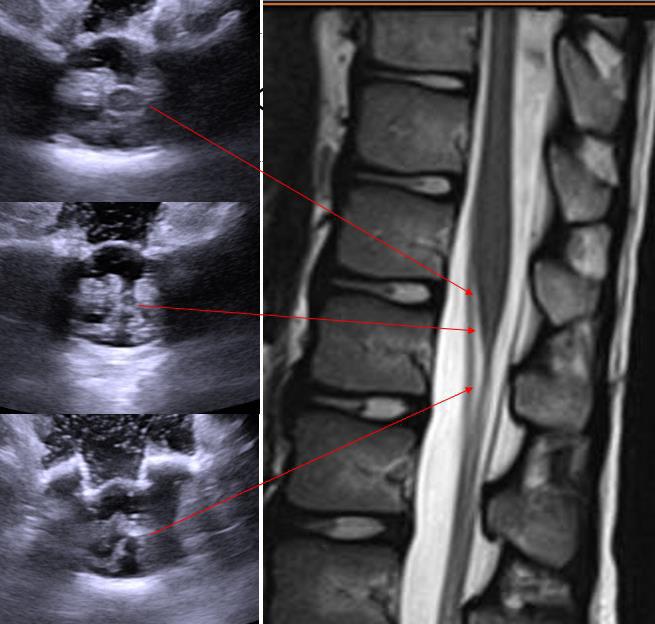

Functional mobility level and baseline gait quality are both important factors to predict gait outcomes after SDR. If candidates are well selected, SDR can be a successful intervention to improve gait both in children with spastic diplegia.

Adductor Longus L2, L3

Vastus Lateralis L3,L4

Tibialis Anterior L4, L5

Peroneus longus L5, S1

Gastrocnemius S1, S2

Abductor hallucis S1, S2

Sphincter S2